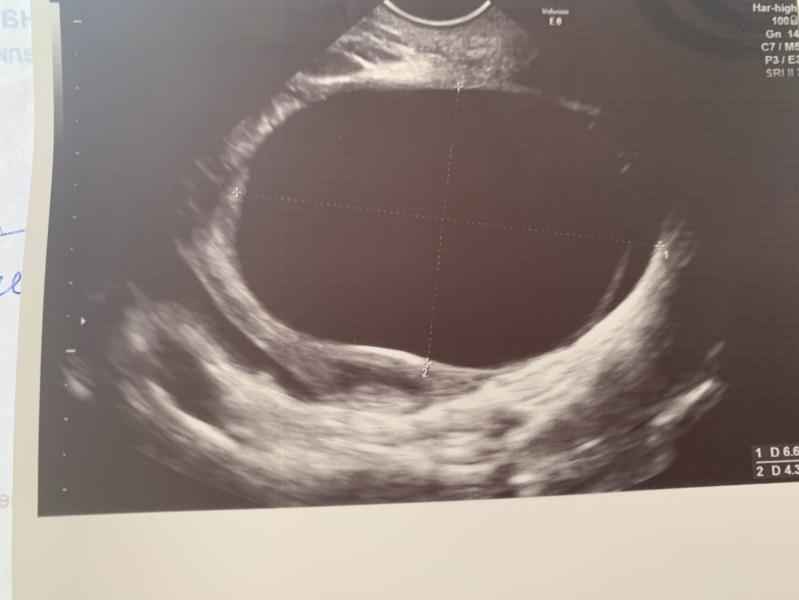

Девочки, у меня беременность 4-5 недель, на УЗИ обнаружили кисту желтого тела в правом яичнике 6 см😭😭врач сказала, не переживать соблюдать полный покой, в том числе половой до 12 недели и пить дюфастон, должна пройти! Но я что-то прочитала и поняла, что это очень плохо и рвануть может в любой момент 😭😭😭 У кого такое было, поделитесь опытом?

Здравствуйте, подскажите, как решился вопрос с кистой... у меня беременность 5 недель и нашли кисту в яичнике 5 см